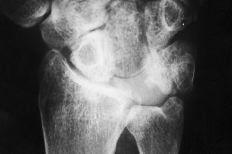

Figura 1. Artroplastia de silicona en semilunar.

Figura 4. Radiografía posteroanterior de muñeca donde se muestra una luxación cubital del implante junto con un colapso carpiano y una traslación cubital.

Figura 5. En la radiografía de perfil se aprecia la inestabilidad en DISI del implante.